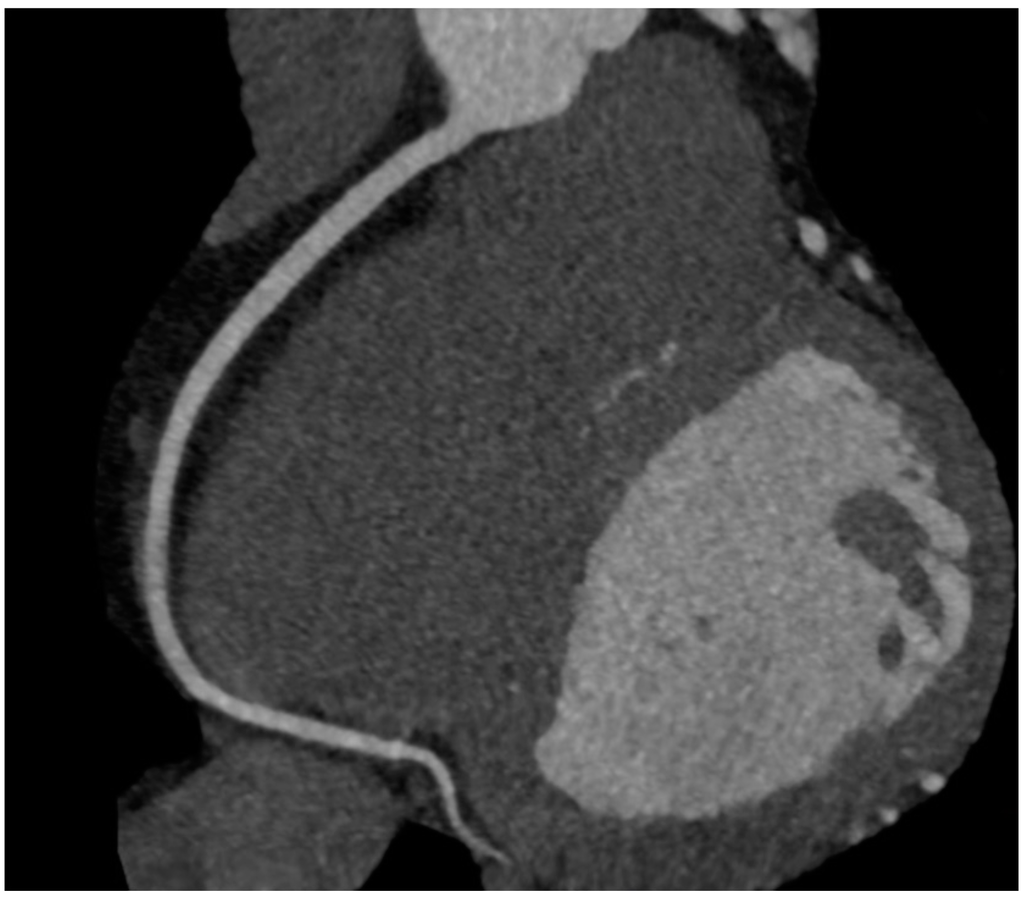

6. Imaging of Coronary Plaques and Stenoses

7. Qualitative Plaque Characterization